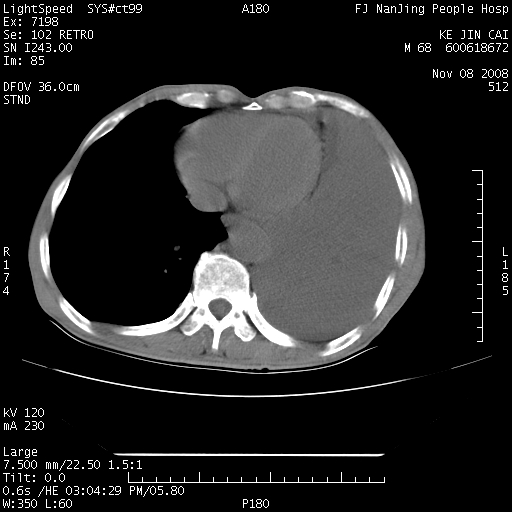

是个很有看头的病例,咋人气那么不旺?没多少人兴趣呢?这个病例几大怪:1   恶性肿瘤侵犯心肌左房怪,心肌一般不会被恶性肿瘤侵犯吧?2   左下肺均匀实变怪,内无含气,有别一般不张实变,含气肺泡完全为液体取代,而非一般不张实变的肺萎陷,冷不丁还以为是肿大的脾脏3   肿瘤本身怪,像tb肺不张4   这么有看头的病例没人气怪。呵呵。

左肺恶性肿瘤侵犯肺动脉,左心房内瘤栓,胸膜转移。